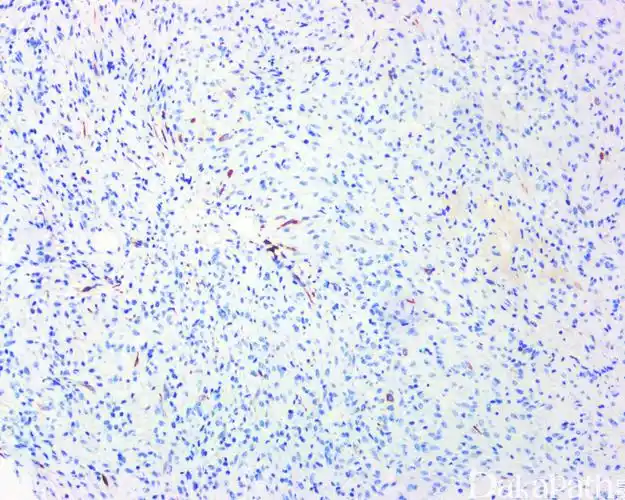

术后梭形细胞结节